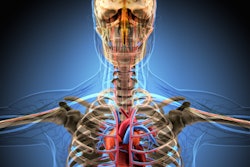

By all accounts, imaging has a big future in virtual autopsy, and CT in particular seems headed for a major role. Investigators are finding that noninvasive virtual exams can often do what traditional autopsy cannot, notably in identifying the dead and pinpointing the causes of death.

For most applications, investigators are finding CT to be the fastest and most accurate modality available to carry out this work.

As for CT, its speed, subtle grayscale, and ability to depict 3D relationships are enormous advantages. Skeletal trauma, for example, can be depicted in ways that conventional autopsy can't replicate.